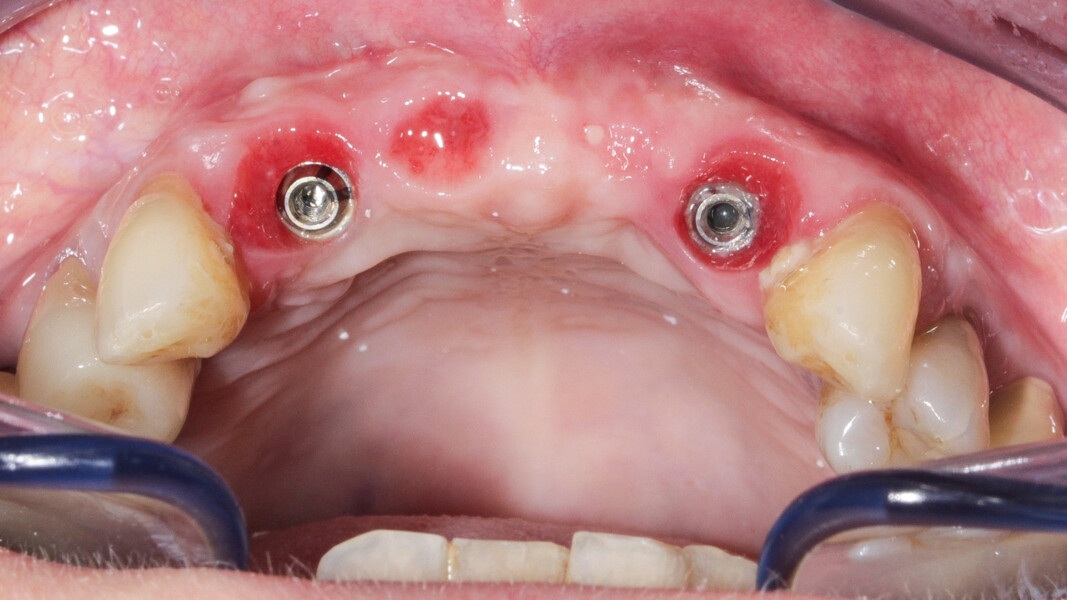

Nous réalisons un lambeau avec une incision crestale décalée en palatin en 11 et 21, sulculaire en 12, 13, 22, 23, en prenant soin de préserver les papilles interdentaires, ainsi que deux décharges verticales en distal des canines. Nous réalisons un décollement de pleine épaisseur (Figs. 28 et 29). Les dents (12, 22 et 18) sont facilement extraites et les alvéoles curetées avec soins. Deux implants (4*13) sont positionnés dans la paroi palatine des alvéoles, il subsiste une déhiscence vestibulaire en 22. Les racines de 12, 22 et 18 sont séparées dans le sens de la longueur. Les racines préparées comme indiqué ci-dessus, sont vissées en vestibulaire et en occlusal de la crête, au moyen de vis d’ostéosynthèse (diamètre 0,9 mm), afin de reconstruire la crête osseuse au niveau des inters de bridge ainsi que la paroi vestibulaire de la crête au niveau de 22 (Figs. 30 et 31). Le gap vestibulaire entre les implants et la crête ainsi que l’espace entre la crête et le greffon au niveau de 21, sont comblés avec un matériau d’origine synthétique (Collapat II Symatese). Le lambeau est tracté, suturé coronairement avec un fil tressé synthétique 5.0 (Fig. 32). Des piliers coniques droits pour prothèse plurale transvissée sont posés, et une empreinte prise à la fin de l’intervention (Fig. 33). Un provisoire est réalisé dans la journée par notre laboratoire de prothèse et posé le soir même. (Figs. 34 et 35)

Les sutures sont retirées à 15 jours. Un contrôle de la bonne ostéointégration des implants est réalisé à 2 mois postopératoire (Figs. 36 et 37). La réalisation de la prothèse d’usage par notre correspondant intervient à 9 mois postopératoire (Fig. 38).